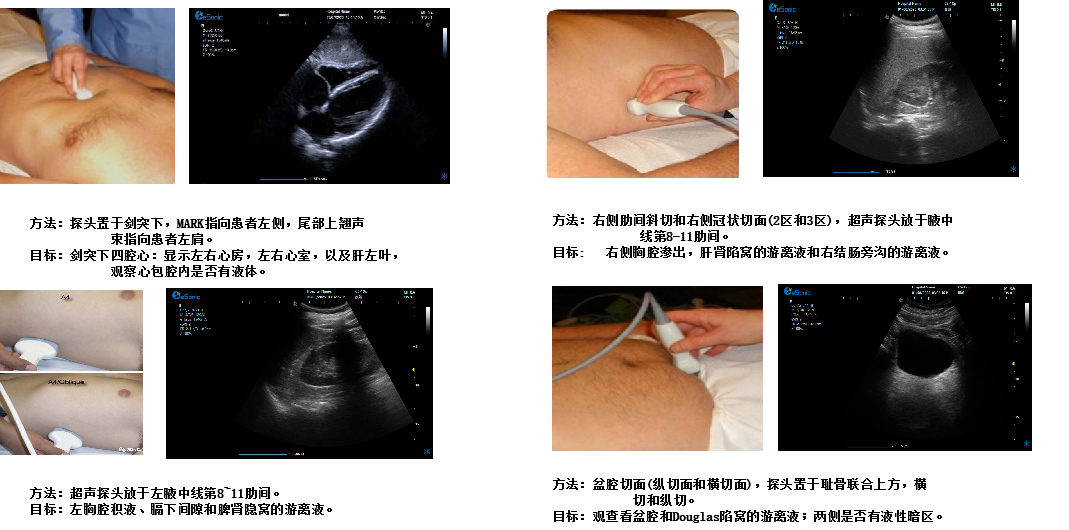

创伤评估FAST

剑突下四腔心切面

扫查方法:探头置于剑突下,声束指向左肩,稍向上倾斜30°,接近心脏冠状切面

超声声像图:图像近场扇尖处可见肝实质反射,此切面可观察左心房、左心室、右心房、右心室、房间隔、室间隔、二尖瓣、三尖瓣等结构。